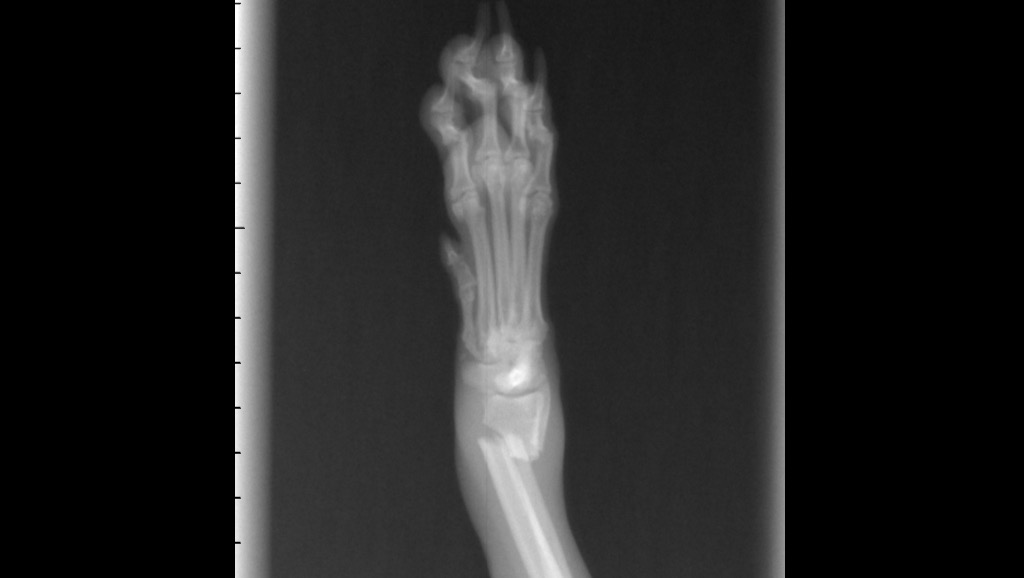

The vets called us and said they need to sedate her to do x-rays. She has two broken bones on her leg. Will attach photos of the X-rays.

The vets said she needs surgery, they sent the X-rays to a surgeon to give us a quote.

Estimate is $3,160.73 for Daisy's surgery where they need to put a plate in.